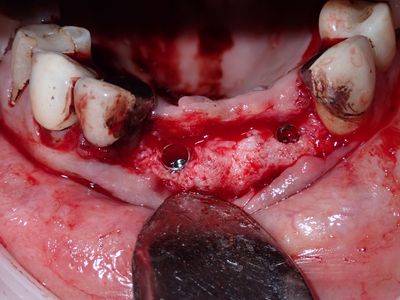

relatively straight forward implant placement in the upper anteriors, densah drills used after 2.2mm twist drill. 21 loss of stablity, spinning, when trying to place deeper, removed implant, deepened osteotomy, implant replaced with good stability.